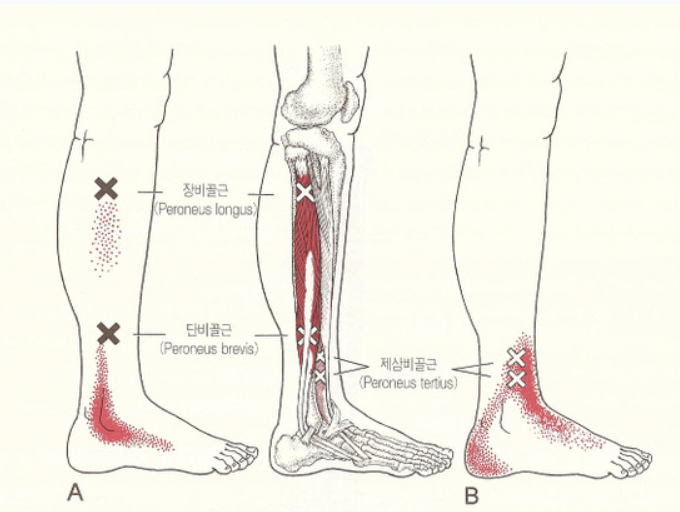

발바닥 신경종 (모튼 신경종)

발가락 사이의 신경이 두꺼워지며 통증을 유발하는 질환으로, 주로 셋째와 넷째 발가락 사이에 발생합니다. 걷거나 신발을 신을 때 찌릿하거나 전기가 흐르는 듯한 통증이 느껴집니다. 하이힐이나 꽉 끼는 신발이 주요 원인입니다.